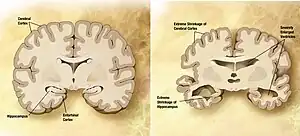

O tipo mais comum de demência é a doença de Alzheimer, responsável por 50 a 70% dos casos.[1][2] Entre outras causas comuns estão a demência vascular (25%), demência com corpos de Lewy (15%) e demência frontotemporal.[1][2] Entre outras possíveis causas, menos prováveis, estão a hidrocefalia de pressão normal, doença de Parkinson, sífilis e doença de Creutzfeldt-Jakob.[11] A mesma pessoa pode manifestar mais de um tipo de demência.[1] Uma minoria de casos é de origem hereditária.[12] No DSM-5, a demência foi reclassificada como perturbação neurocognitiva, com vários graus de gravidade.[13] O diagnóstico tem por base a história da doença e exames cognitivos, complementados por exames imagiológicos e análises ao sangue para despistar outras possíveis causas.[3] Um dos exames cognitivos mais usados é o mini exame do estado mental.[2] As medidas para prevenir a demência consistem em diminuir os fatores de risco como a hipertensão arterial, tabagismo, diabetes e obesidade.[1] Não está recomendado o rastreio na população em geral.[14]

A demência é um termo geral para várias doenças neurodegenerativas que afetam principalmente as pessoas da terceira idade. Todavia a expressão demência senil, embora ainda apareça na literatura, tende a cair em desuso. A maior parte do que se chamava demência pré-senil é de fato a doença de Alzheimer,[23] que é a forma mais comum de demência neurodegenerativa em pessoas de idade. Embora existam casos raros diagnosticados de pessoas na faixa de idade que vai dos 17 anos[24][25][26] aos 50 anos e a prevalência na faixa etária de 60 aos 65 anos esteja abaixo de 1%, a partir dos 65 anos ela praticamente duplica a cada cinco anos. Depois dos 85 anos de idade, atinge 30 a 40% da população.[27]